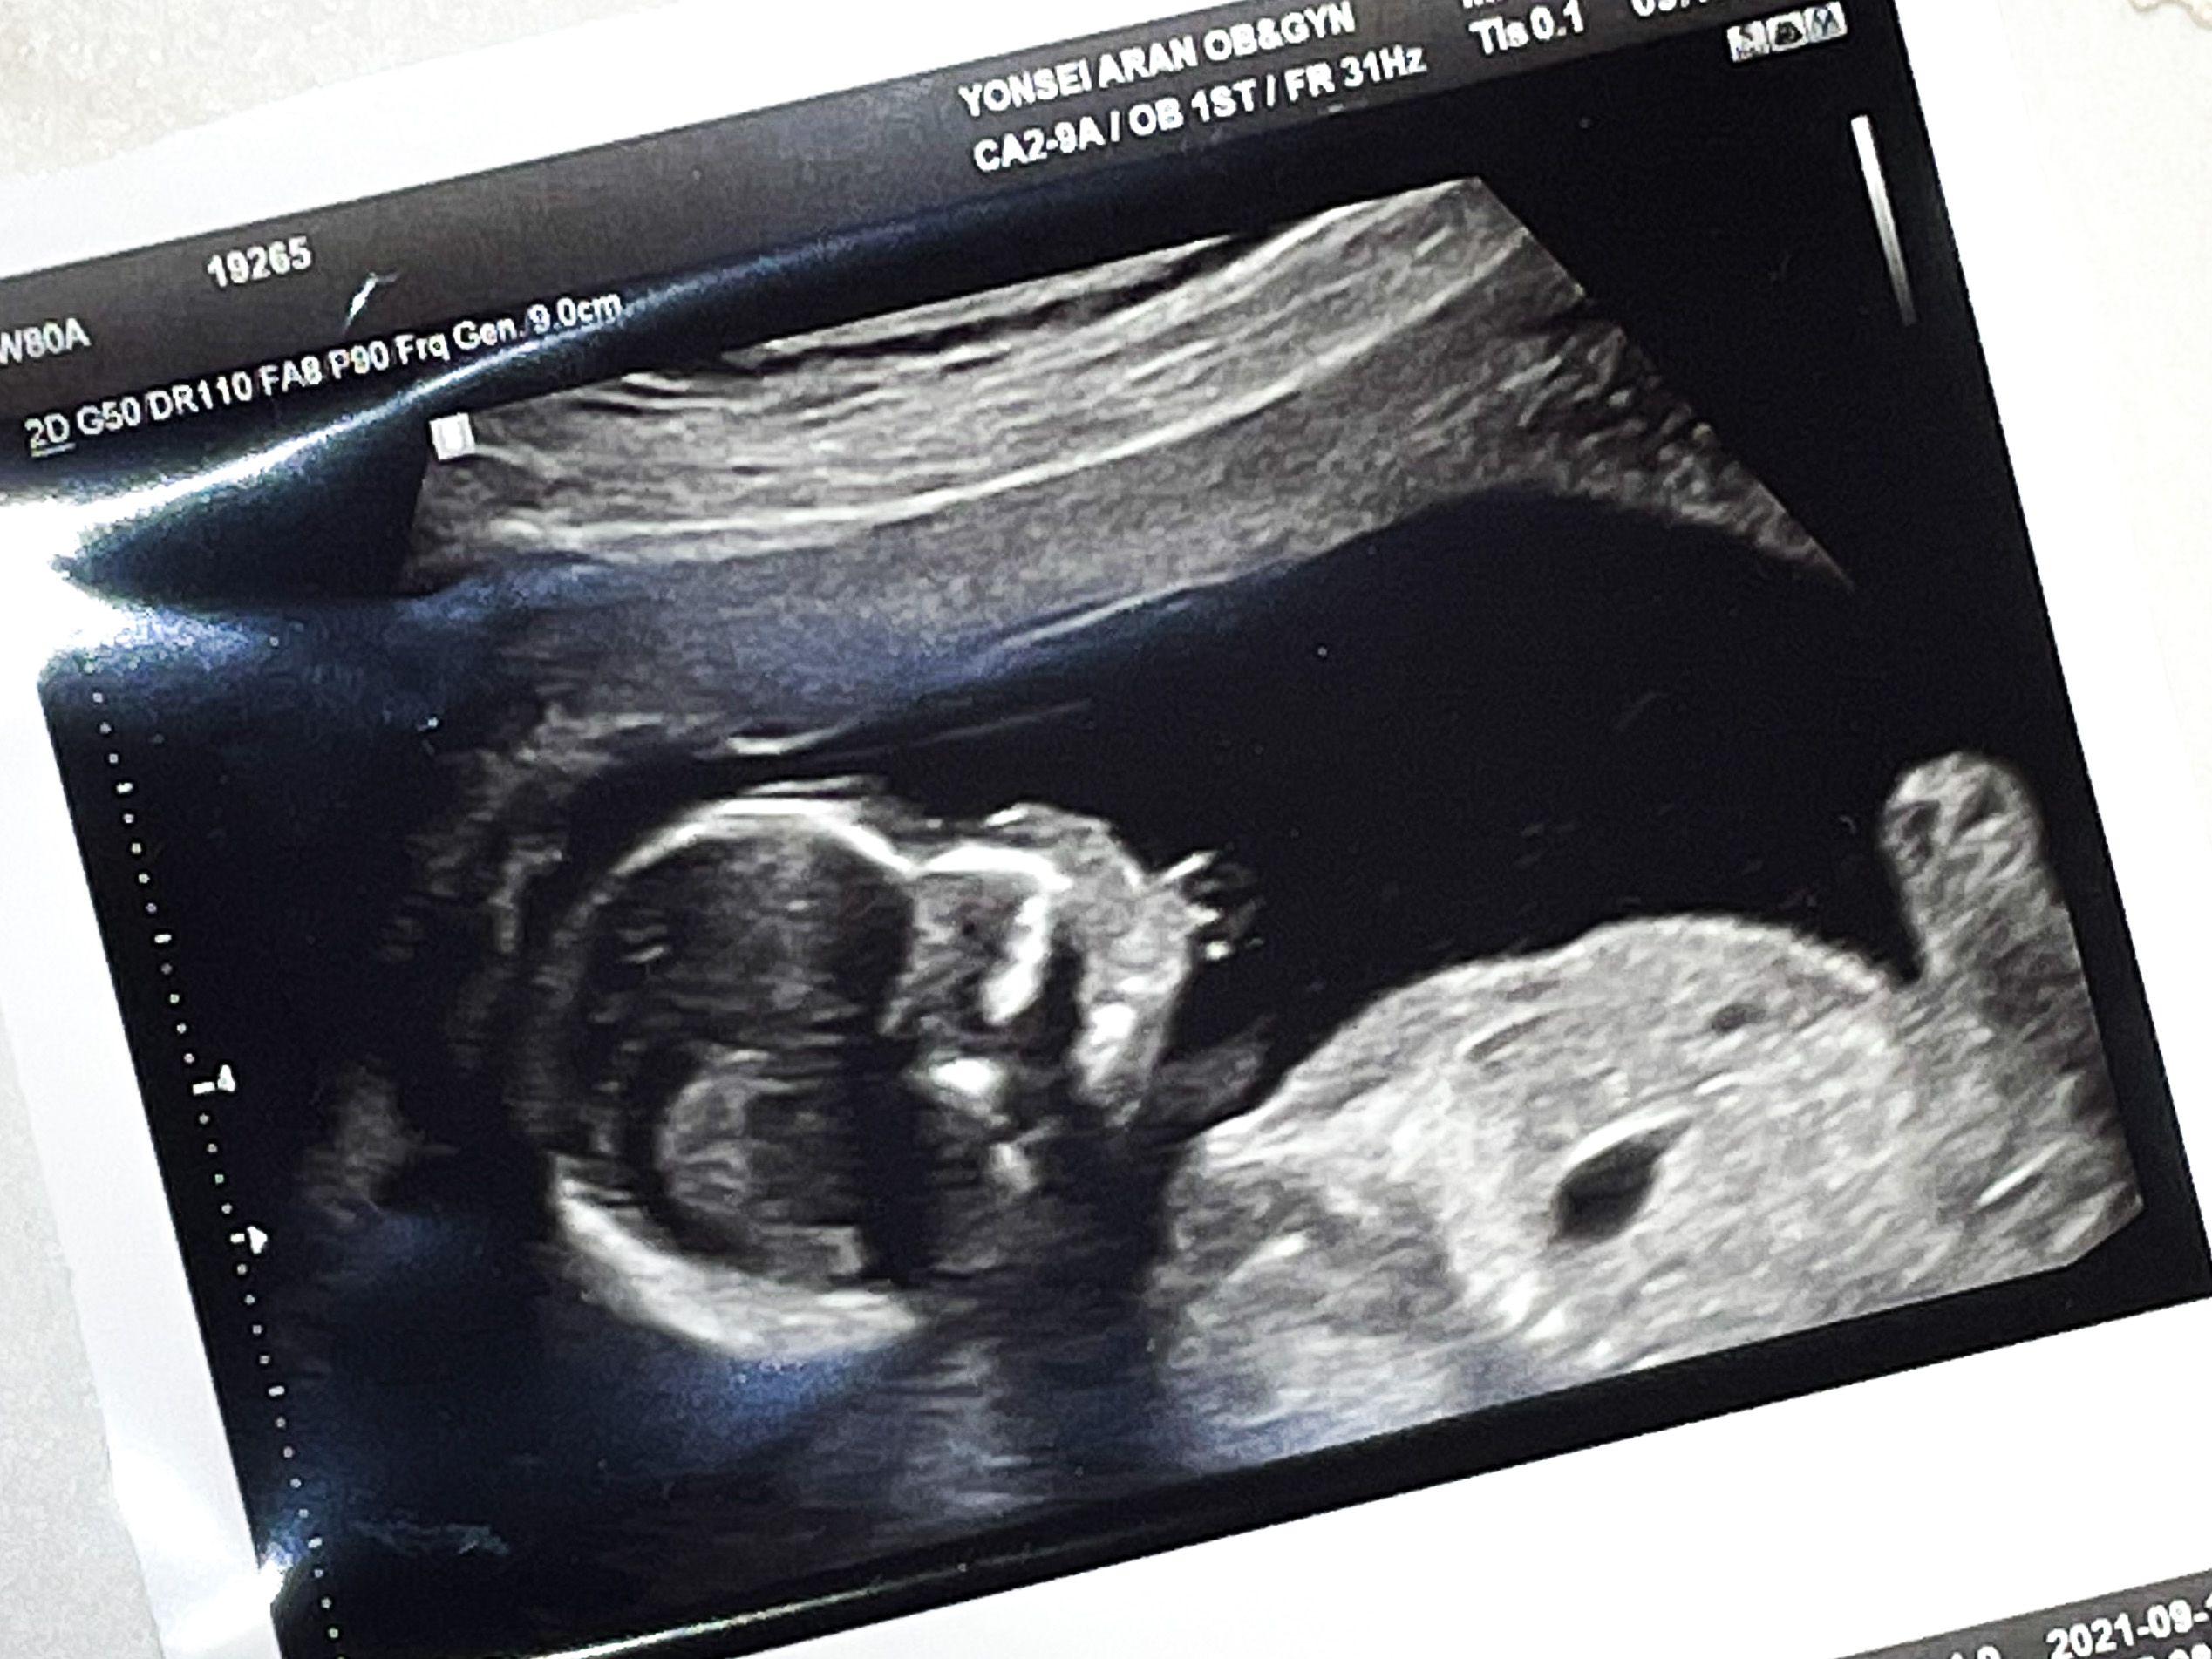

15주 4일 2차 기형아 검사를 받으러 갔다.

먼저 담당 원장님과 초음파를 확인했다.

원장쌤께 혹시 아들인가요..?하고 여쭤보니

아직 안봐드렸었냐며,

바로 초음파로 정확하게 찍어서 프린트 해주셨다.

각도법으로 확인했던 그대로 아들이었다!

(단톡방 마다 저 위에 초음파 사진을 보냈는데 우리 엄마와 시어머니만 뭔지 알아보셨다..ㅋㅋ)